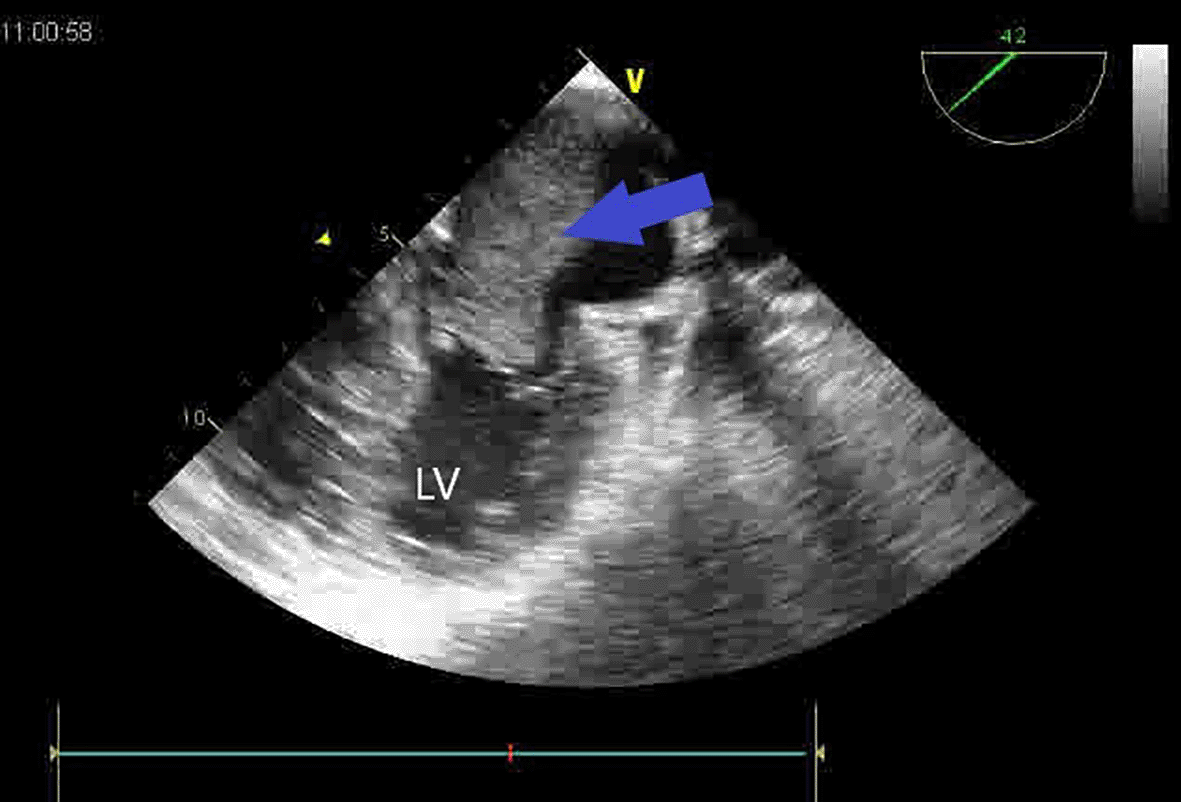

A second huge mass compressed the right atrium posterior wall. Following respiratory stabilization, transesophageal echocardiography confirmed TTE results and revealed an extended mass into LA via the right inferior pulmonary vein (RIPV) (Figure 2). Cardiac computed tomography (CT) revealed a large (100 × 70 × 100) mediastino-pulmonary mass extending to LA via RIPV (Figure 3).